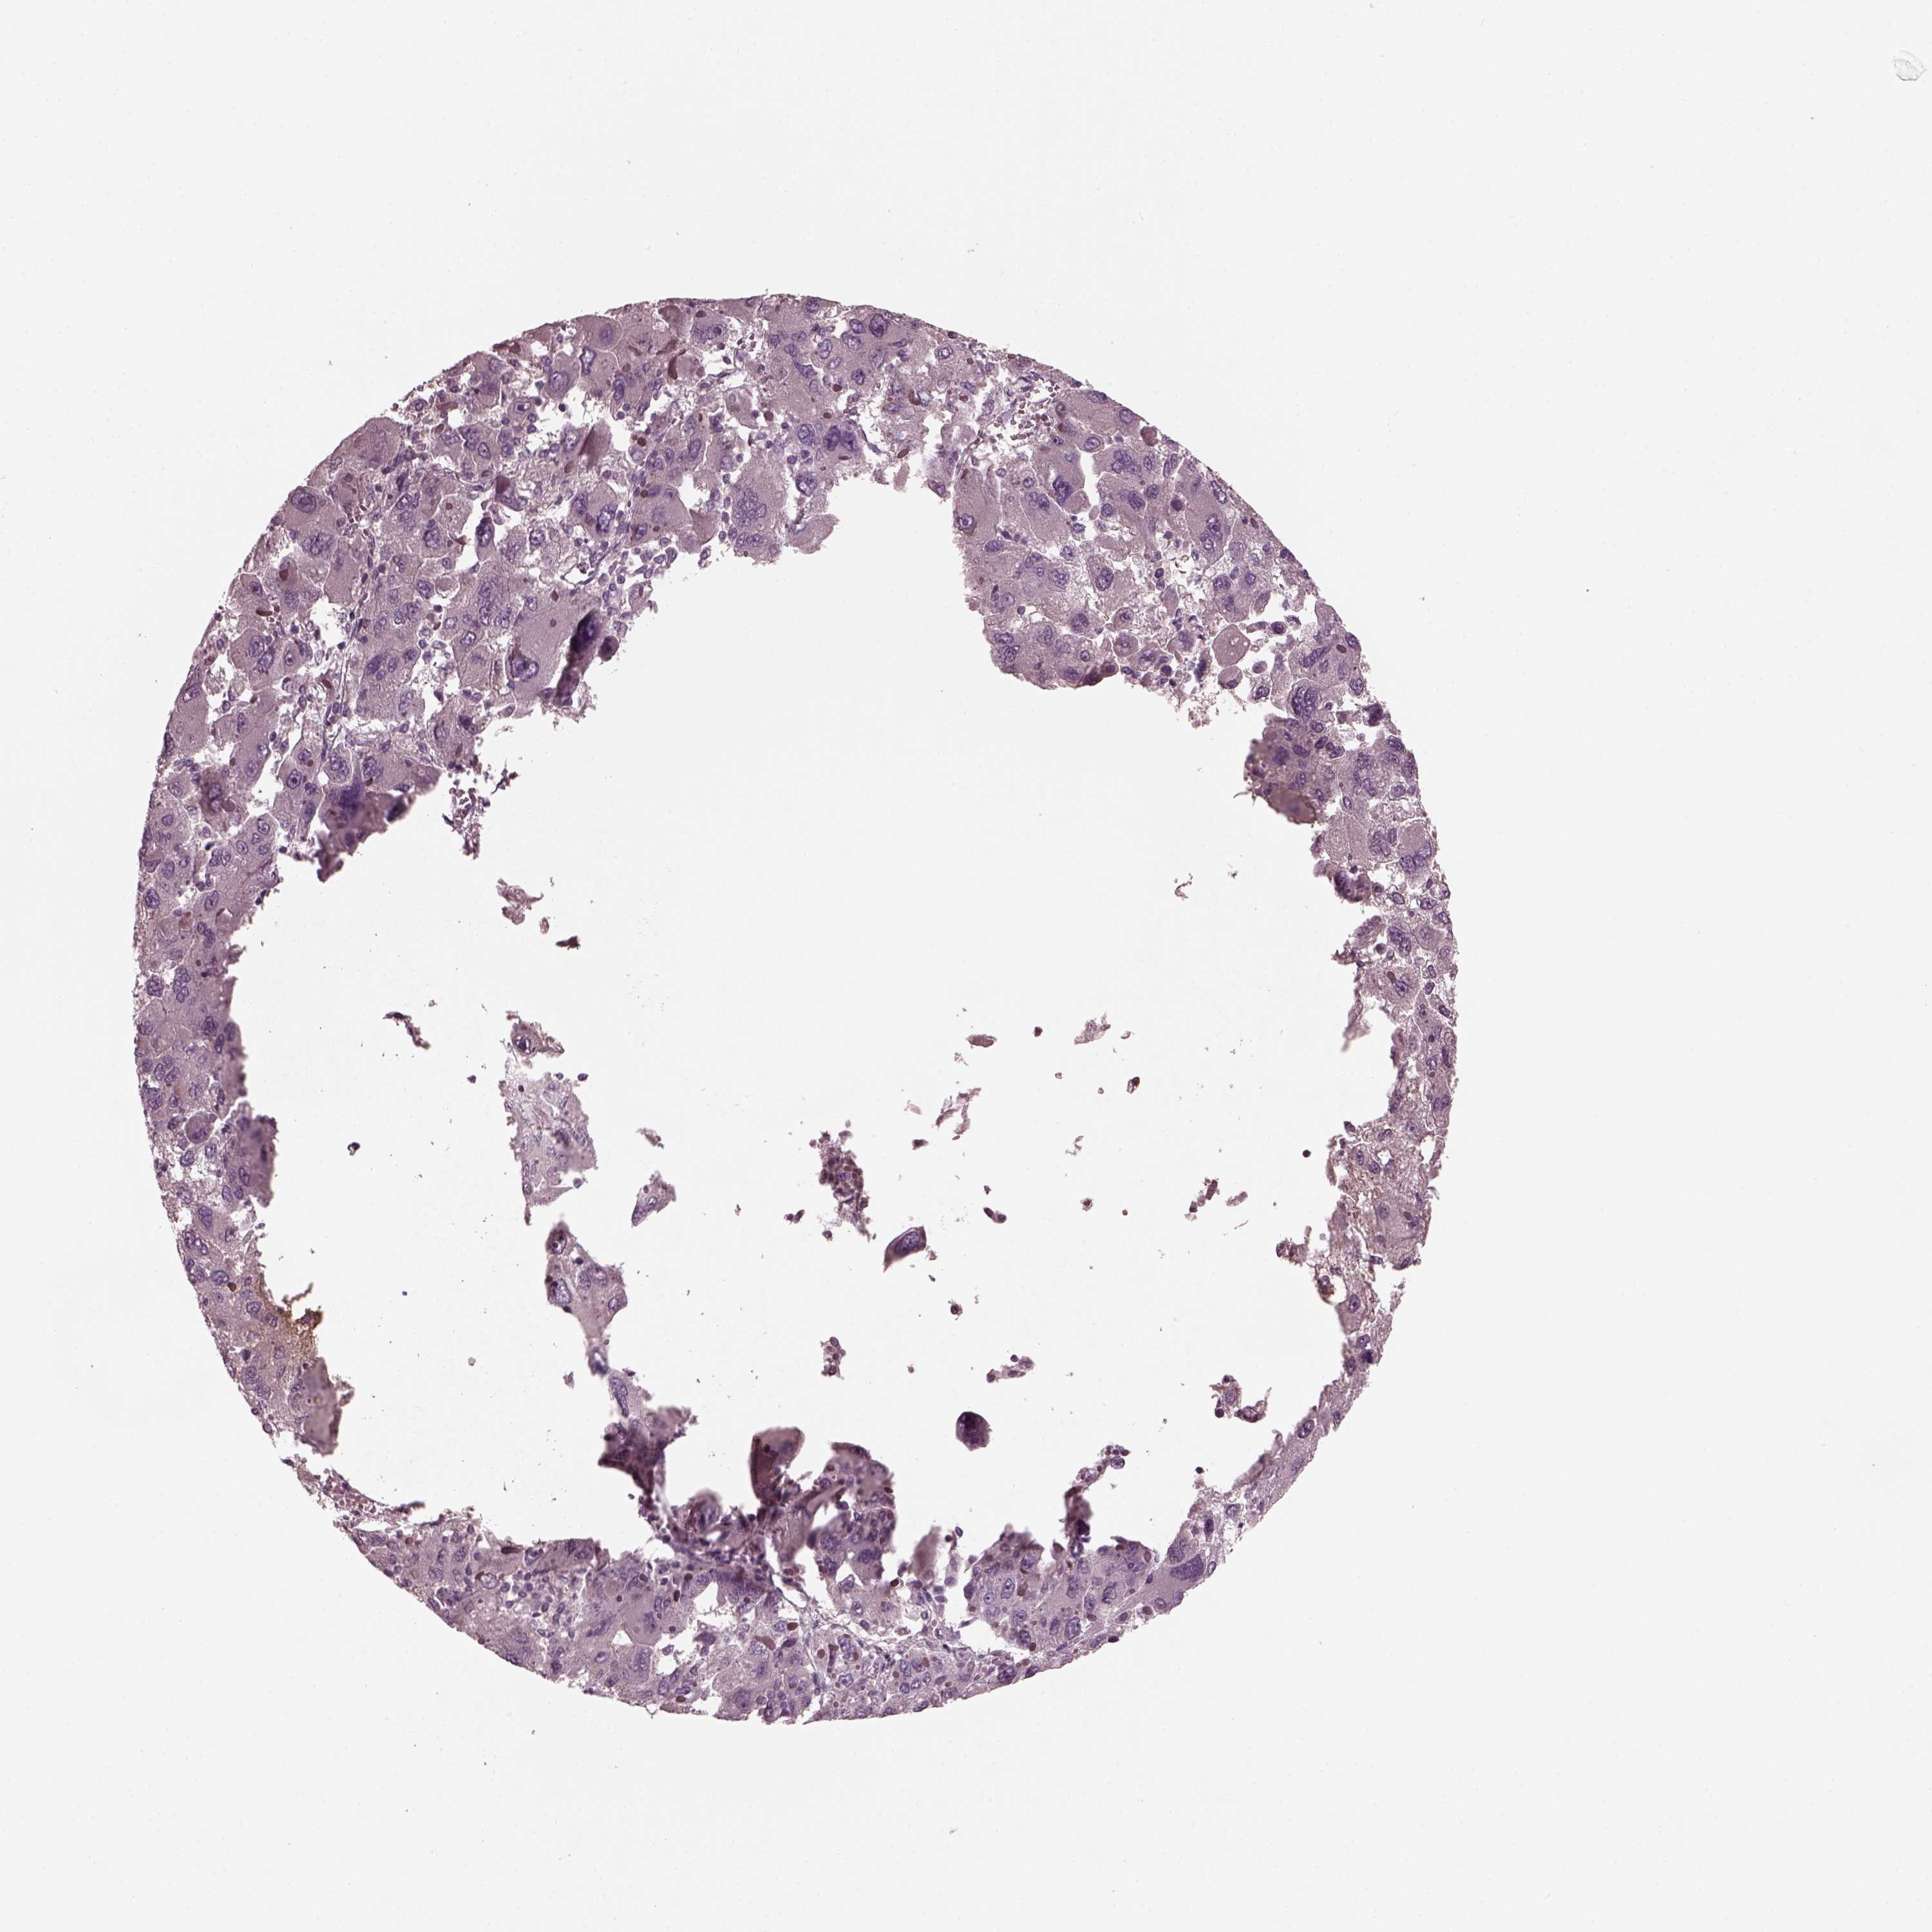

LIVER CANCER - Protein expressioni

A mouse-over function shows sample information and annotation data. Click on an image to view it in a full screen mode. Samples can be filtered based on level of antibody staining by selecting one or several of the following categories: high, medium, low and not detected. The assay and annotation is described here.

Note that samples used for immunohistochemistry by the Human Protein Atlas do not correspond to samples in the TCGA dataset.

Antibody stainingi

Antibody staining in the annotated cell types in the current human tissue is reported as not detected, low, medium, or high, based on conventional immunohistochemistry profiling in selected tissues. This score is based on the combination of the staining intensity and fraction of stained cells.

Each image is clickable and will lead to virtual microscopy that enables deeper exploration of all samples and also displays staining intensity scores, fraction scores and subcellular localization as well as patient and tissue information for each sample.

Antibody HPA058413

Staining

High

Medium

Low

Not detected

Intensity

Strong

Moderate

Weak

Negative

Quantity

>75%

75%-25%

<25%

None

Location

Nuclear

Cytoplasmic/membranous

Cytoplasmic/membranous,nuclear

Carcinoma, Hepatocellular, NOS

Cholangiocarcinoma